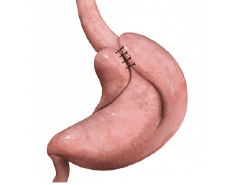

Vesícula Biliar

La cirugía de la vesícula biliar, llamada Colecistectomía Laparoscópica, es el procedimiento por el cual se lleva a cabo la extirpación de la vesícula. Este tipo de cirugía está indicada cuando la vesícula biliar contiene litos o piedras en su interior causando un proceso inflamatorio agudo o crónico llamado Colecistitis Litiásica. Los síntomas dependerán si se presenta el cuadro clínico de manera crónica con dolor abdominal de larga evolución en región subcostal derecha, nausea, vómito o si los síntomas se presentan de manera súbita con dolor abdominal de gran intensidad requiriendo de manejo quirúrgico de urgencia.

La cirugía se realiza mediante laparoscopía a través de 3 pequeñas incisiones de 5 y 10 mm, extrayéndose la vesícula por una de estas heridas, lo cual permite excelentes resultados estéticos, una pronta recuperación con mínimo dolor y una rápida reintegración a sus actividades. A pesar de que es un padecimiento frecuente, se requiere amplia experiencia para evitar complicaciones o lesiones desencadenadas durante la cirugía, es por ello que ofrecemos una atención de alta calidad, con el mejor equipo médico y técnico para poder resolver esta patología con la menor probabilidad de riesgos o complicaciones y con una recuperación prácticamente inmediata.